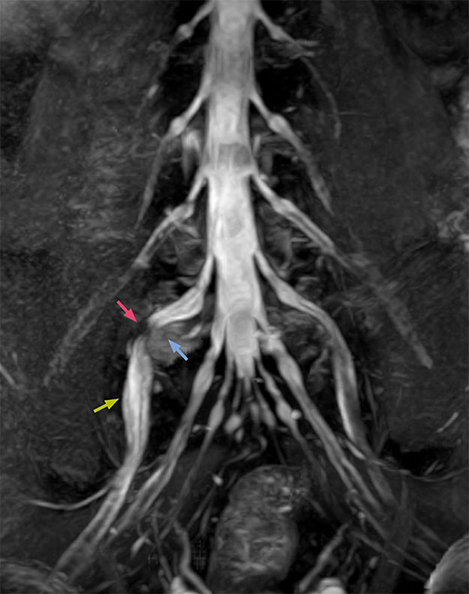

“In patients with lower extremity neurological symptoms, NerveVIEW helps us to determine the disease matching the patient’s symptoms by directly visualizing the nerves. We use the sequence mainly, when there is suspicion of intraforaminal stenosis, extraforaminal stenosis or lateral disc herniation, which is often based on routine T2- and T1-weighted images. Additionally, the excellent depiction of the course of nerves makes NerveVIEW a good navigator when applying treatment such as block therapy or surgery.”

“In such case, we would then browse through axial T2-weighted MR images slice by slice and mentally reconstruct the actual situation based on both radiculography and MRI. Fortunately, NerveVIEW can now very well show nerve courses and presence of nerve compression or edema in one single image series.” “We have often seen NerveVIEW directly depict details of the nerve compression that were not observed by radiculography. Therefore, we think that with NerveVIEW we can reduce the number of invasive examinations, especially for some patients with lumbar plexus symptoms.”

“Before NerveVIEW, diagnosis by MRI alone was sometimes difficult, unless there was a strong suspicion based on clinical symptoms,” says Shoji Yabuki, MD, DMSc, Orthopedic surgeon at Fukushima Medical University School of Medicine. “This is why we routinely perform selective lumbosacral radiculography (nerve root block) and x-ray in such cases. However, radiculography can only depict nerves as far as the contrast agent reaches. When a nerve is distorted by compression, the contrast agent will not pass through this compressed area, preventing us from evaluating the full nerve compression.”

“NerveVIEW can clearly show nerve courses and presence of nerve compression. However, when multiple abnormalities are seen, it can still be hard to determine which nerve is causing the symptoms,” says Dr. Yabuki. “In our experience so far, we see abnormal findings on NerveVIEW in about 70% of elderly patients. As the pain is usually caused by only one nerve, we thus need to find the exact corresponding nerve.” “With a nerve root block, the patient's pain is improved by infiltration of local anesthesia directly around the nerve root considered to be responsible. Knowing such nerve root block findings prior to image interpretation, helps to easily recognize abnormal findings on NerveVIEW as well. In other words, without a priori knowledge, based on symptoms and/or nerve root block findings, we must be aware of the possibility of overdiagnosis.”